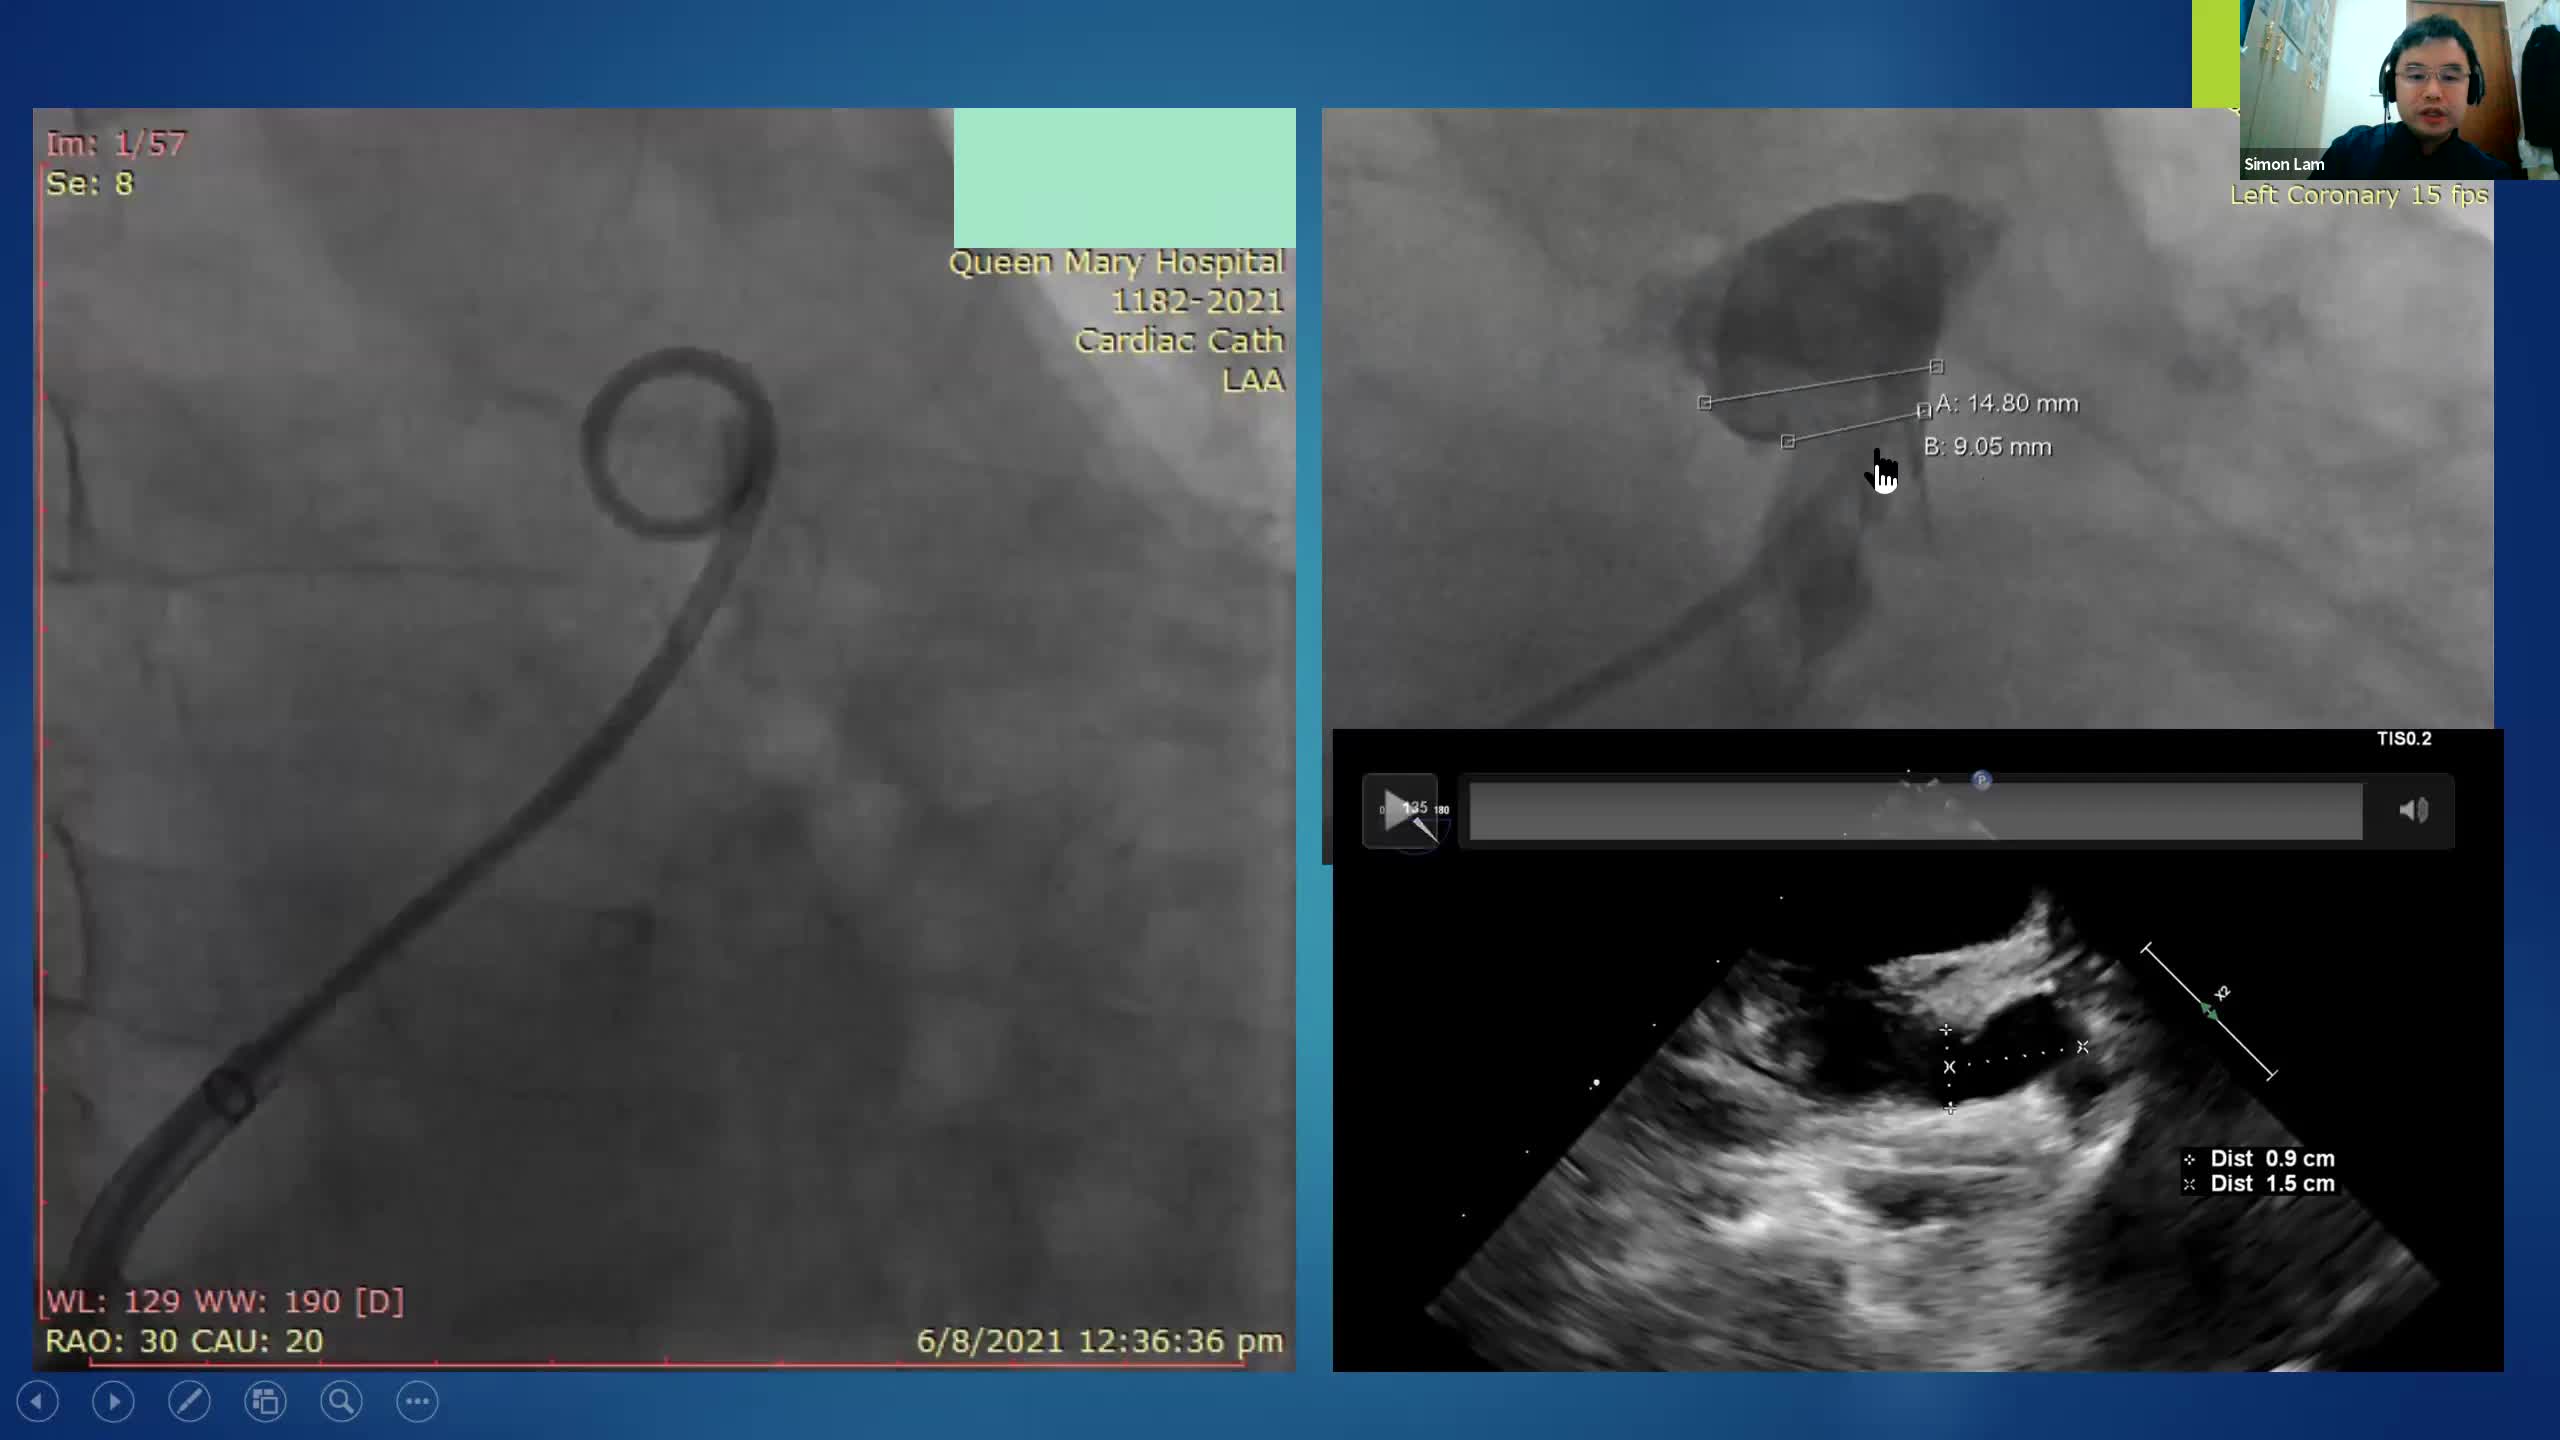

CSI CATHLAB LIVE - INTER-ATRIAL SHUNT FOR DECOMPRESSION OF THE LEFT ATRIUM IN A PATIENT WITH VERY SEVERE HEART FAILURE WITH THE AFR DEVICE